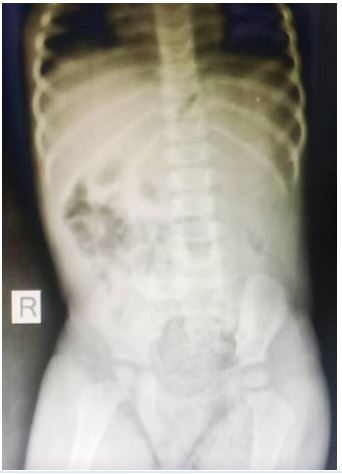

She presented with a plain abdominal radiograph which showed a FB (nail) in the body of the stomach (Figure 1) This was done about 6 hours prior to the presentation at our facility. A repeat radiograph done at the presentation showed the FB (nail) at the region of the terminal ileum (Figure 2). She was commenced on nil per oral, intravenous fluids and monitoring (clinical and radiological). She had two additional plain abdominal radiographs, (Figure 3, 24 hours on admission) and (Figure 4, on day 3). The vital signs remained stable and the abdominal examinations remained equivocal throughout the period of admission. She was discharged following a repeat radiograph which showed no evidence of FB in the GIT.

Figure 3: AP + Lateral view of plain abdominal radiograph. (24 hours admission).